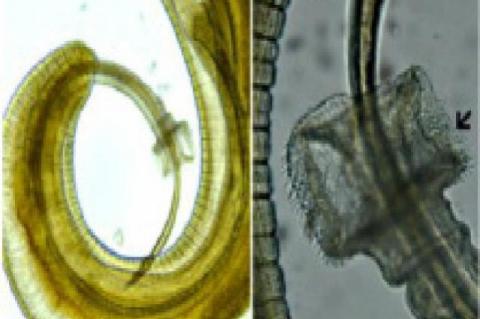

Parasitoses and Histopathological Consequences of Trichuris trichiura (Nematoda: Enoplida) in Rodents, Rattus rattus (Mammalia: Rodentia)

Sushil Kumar Upadhyay,Sanjay Shamrao Nanware

Asian J. Biol. Life Sci.,9(1):74-78

DOI: 10.5530/ajbls.2020.9.11